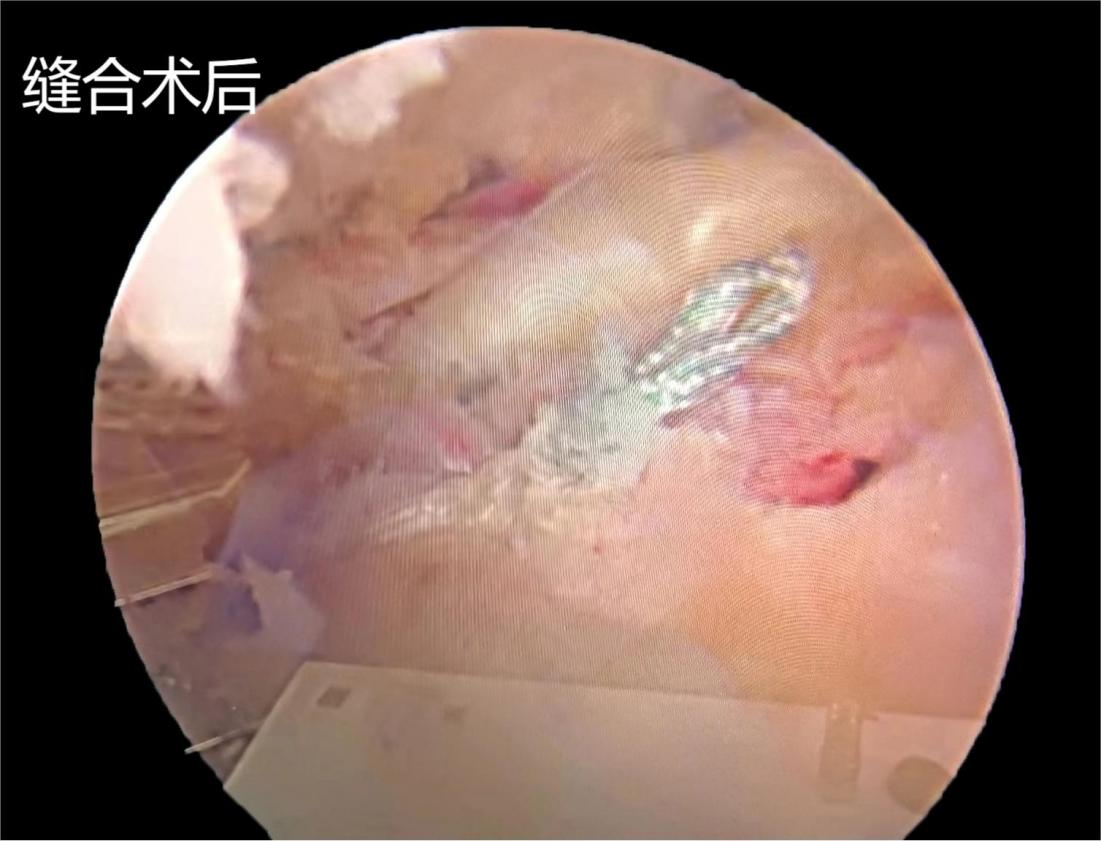

患者系“右肩疼痛,活动受限三个月”入院,入院后完善相关检查示:右冈上肌腱巨大撕裂并回缩,肩峰间隙狭窄。专科查体:右肩活动受限,落臂征阳性,空罐试验阳性,拿破仑试验阳性,肩峰撞击试验阳性。患者右肩疼痛难忍,夜间疼痛明显,严重影响睡眠,生活质量差。在全麻下关节镜下行肩袖修补术、肩峰减压成形术,术中见肩袖间隙组织增生,关节囊稍增厚,滑膜组织充血水肿,在关节镜可视化下,利用等离子射频消融电极松解肩袖间隙,切除充血滑膜组织,镜头转向肩峰下,见冈上肌腱巨大撕裂,显露肩峰,见肩峰骨赘形成,刨削增生骨赘,肩峰下间隙明显增大,冈上肌腱附着处植入内排锚钉,用缝合钩带线缝合肩袖,术后患者右肩疼痛明显缓解,术后肩关节外展包固定。